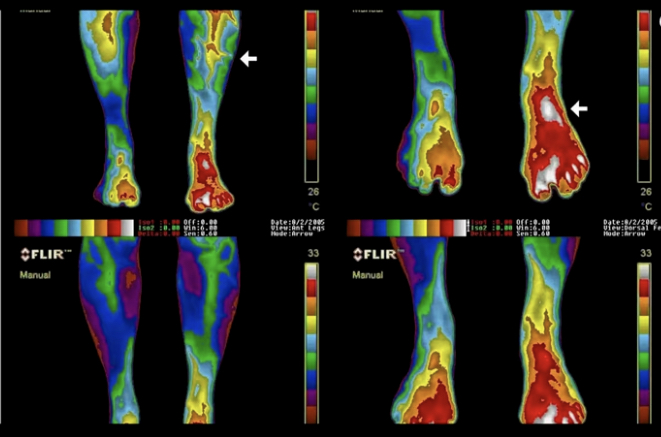

Sursă photo: Gaia